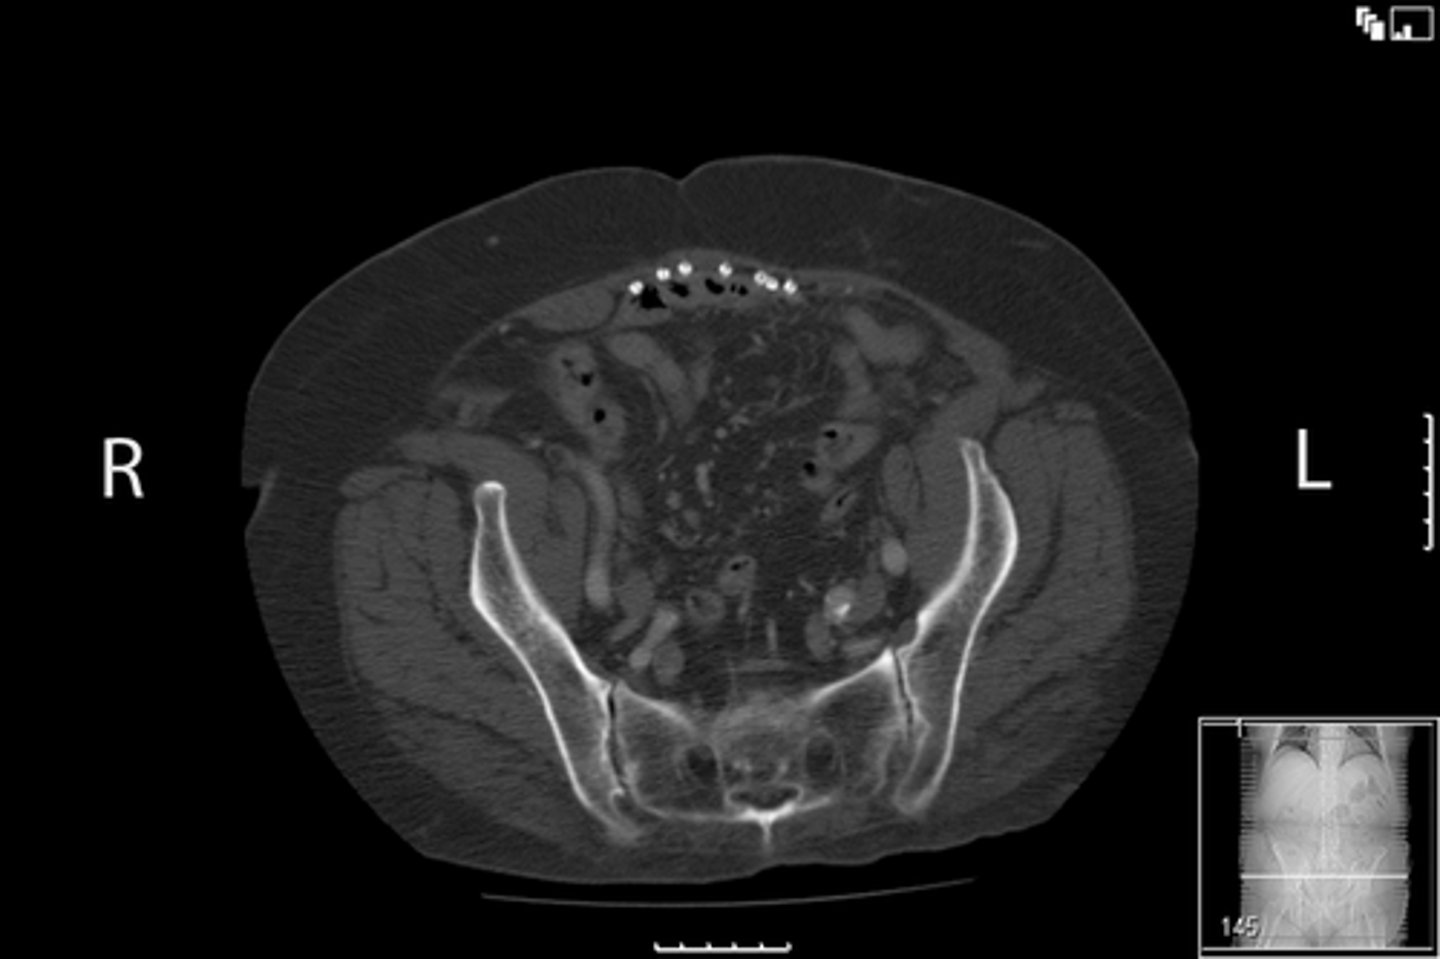

Axial bony pelvis CT

What is the image?

L ilium

What is indicated in the image?

L sacroiliac joint

R ilium

R sacroiliac joint

Sacrum